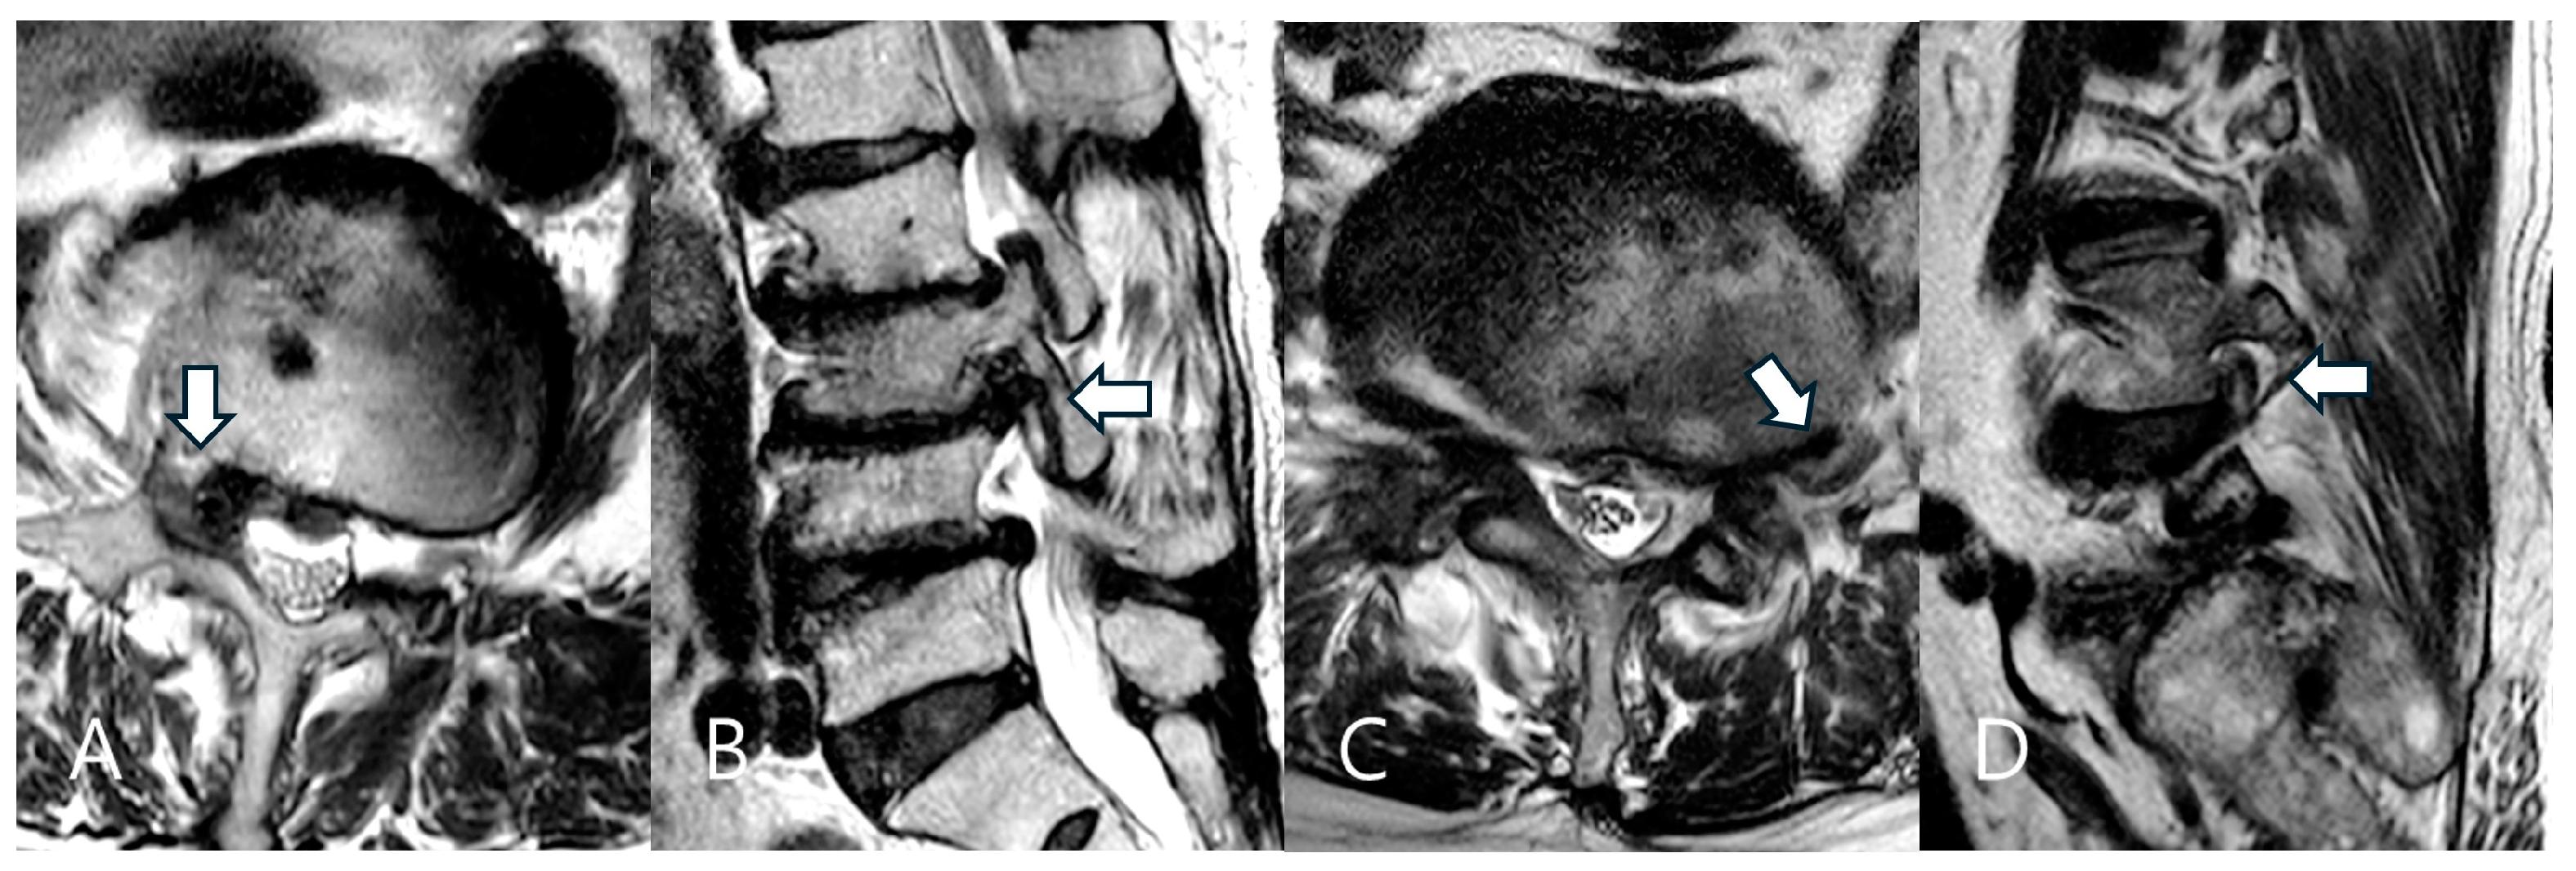

This retrospective study included patients diagnosed with far-lateral LDH who underwent TELD under local anesthesia at a single tertiary hospital between January 2018 and December 2021. The Institutional Review Board of Gachon University Gil Medical Center approved the study (GDIRB2023-210, 24 June 2023), and written informed consent was obtained from all participants. Patients were included if they presented unilateral radiculopathy refractory to conservative treatment for at least six weeks and had MRI-confirmed single-level far-lateral LDH that occurred lateral to the spinal canal covering the foraminal and/or extraforaminal region [23,24,27] (Figure 1). Patients with intracanalicular LDH confined to the spinal canal (central or subarticular LDH), previous lumbar surgery at the same level, spondylolisthesis exceeding Grade I, or severe spinal deformities were excluded.

Figure 1.

Two types of far-lateral lumbar disc herniation (LDH) based on the herniation zone. Foraminal LDH in a 75-year-old female patient at the right L3–L4 level (A,B). The herniated disc is located in the foraminal zone (arrow). Extraforaminal LDH in a 70-year-old male patient at the left L4–L5 level (C,D). The herniated disc is located in the extraforaminal zone (arrow).